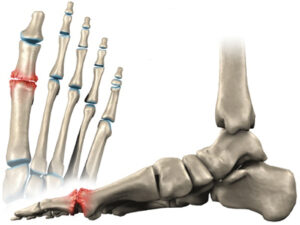

El Hallux Rigidus es una patología que impide la dorsiflexión de la articulación del Hallux (dedo gordo del pie).

Se caracteriza por una artrosis osteofítica, degenerativa y anquilosante de la primera articulación metatarsofalángica. El Hallux Rigidus es uno de los problemas más frecuentes del primer dedo del pie.

En estadios avanzados, a la hora de caminar no se puede ejecutar el paso correctamente, limitando así la fase en la que el pie despega del suelo (3º rocker o balancín del pie).

Esta articulación es fundamental a la hora de levantar el talón al realizar el paso, así como para saltar o correr. Además, nos ayuda a mantener el equilibrio cuando estamos de pie. Por esta razón, el diagnóstico precoz y un tratamiento adecuado son decisivos para corregir y evitar la evolución del Hallux Rigidus.